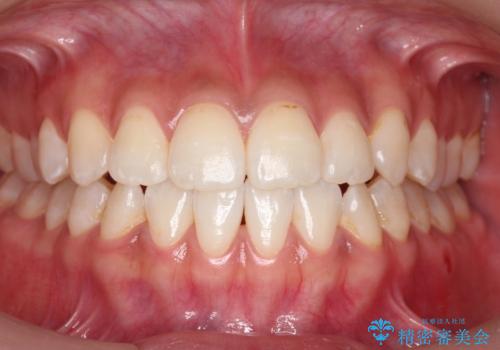

【モニター】左右のクロスバイトをインビザラインできれいに改善